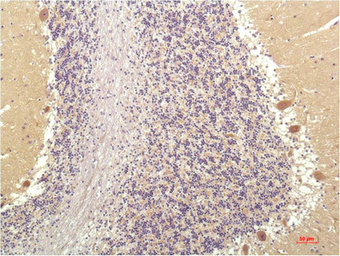

IHC-P analysis of human brain tissue using GTX34195 SGK1 antibody [4D12].

Dilution : 1:200